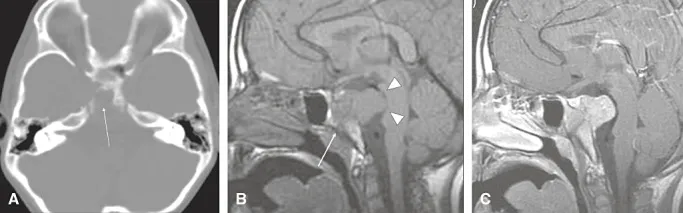

神经影像学检查显示斜坡骨质破坏性病变,位于蝶鞍平面以下,伴巨大软组织成分向颅内扩展。病灶呈实性、分叶状,信号均匀,明显强化,T2信号相对较低提示细胞密度高。平扫CT(图1A)显示斜坡广泛骨质破坏,病灶位于斜坡中心(箭头),无骨性或软骨样基质。磁共振成像(MRI)显示病灶信号均匀,平扫T1加权像呈等信号(图1B),T2加权像呈低信号。病灶呈均匀强化(图1C)。MRI进一步显示该分叶状实性肿块取代了蝶枕软骨结合周围斜坡脂肪骨髓的正常高信号(图1B箭头),向背侧扩展至桥前池,压迫脑桥(图1B箭头),并侵犯右侧海绵窦,部分包绕颈内动脉。

图1